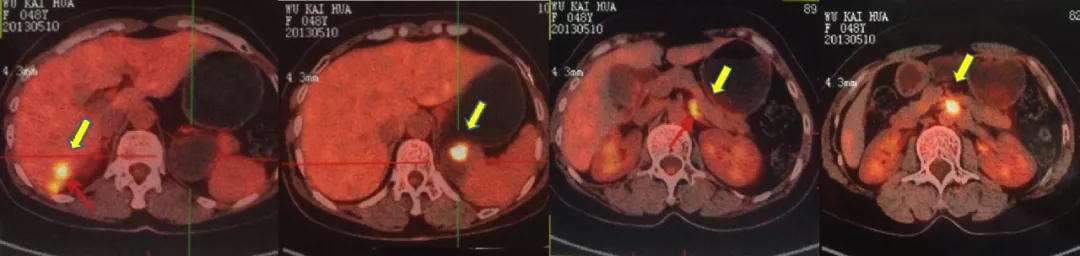

2014.6.11 CT:脾周囊性低密度灶2.4*2.7cm,较2014.2.26增大,腹主动脉旁肿大淋巴结,考虑“卵巢癌复发”。

CT检查结果

第3次复发(PFI3rd=23个月)

2016.10.14查PET-CT: 盆腔内软组织密度灶,FDG代谢异常增高,考虑转移灶;右肝后下段包膜处结节样、片状转移灶;左肾前方斑片状,腹主动脉管壁处(L3椎体水平)FDG代谢轻度增高,考虑肿瘤活性组织存在。

PET-CT检查结果